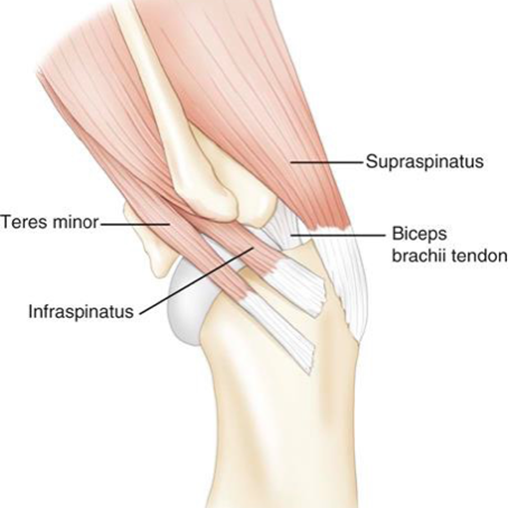

Basic Anatomy

The shoulder is on the face of it very simple with the head of the humerus acting as the ball and the glenoid of the scapula the socket for a simple ball and socket joint. Dogs don’t have a clavicle. The simple nature of the bony anatomy means that the stability and function to the shoulder is closely controlled by ligaments, tendons, muscles and the joint capsule and it is injury to one of these structures that is the cause of the lameness. This is important to consider because lameness is often associated with dysfunction, imaging soft tissue structures is more difficult than the bones and healing takes a long time. Typically a bony fracture can heal to the point of vigorous use in 12 weeks, soft tissue injuries will take up to 6 months sometimes.

This list is not exhaustive and biceps tendon luxation, infraspinatus bursal ossification, traumatic cartilage injury, shoulder dysplasia, Teres Minor ligament injury, tumors and fractures are all less likely causes of lameness.